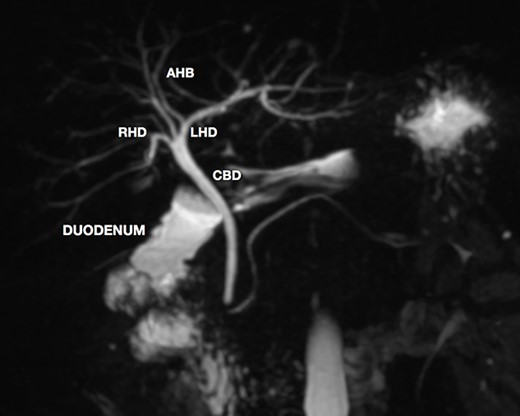

A magnetic resonance cholangiopancreatography (MRCP) confirmed the absence of gallbladder and of the cystic duct and artery (Figs 4–6). No other abdominal anomaly was identified.

MRCP coronal image showing the intrahepatic biliary tract, with good vision of common bile duct, right and left hepatic ducts and anterior branch duct.